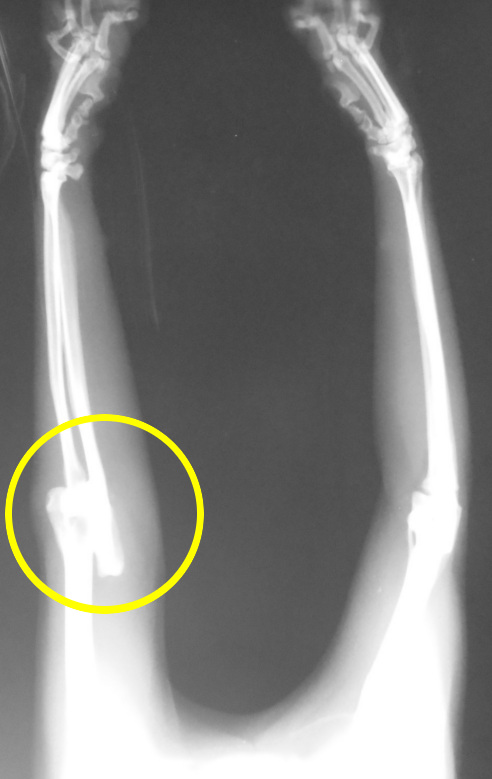

尺骨骨折・肘関節脱臼

手術前

手術後

このネコちゃんは外にも良く出ている子で、早朝帰ってきたら前肢に痛みがあるとのことで来院されました。

レントゲン検査をしてみると・・・、肘から下の腕は2本の骨からできていますが、その内の1本(尺骨)が骨折していました。さらに、前足の肘関節が脱臼して大変な状況です。

事故にあったことが考えられるため、数日様子をみてそれから他に問題がないことを確認し手術を実施しました。

手術は骨の中に金属の棒即ちIMピンを挿入し、次に折れている骨に回転の力がかかった時不安定にならないようにワイヤーで骨折していた骨を固定しました。

肘の関節はめちゃくちゃになっていたので、丁寧に縫い合わせ、靭帯も裂けていたため強力なナイロン糸で固定して終了としました。皮膚は手術時間の短縮のためにも金属の糸(ステープラー)で縫合しました。

この子は関節の状態が心配だったのですが、その後、肘の関節も全く問題なく、正常に機能することができました。